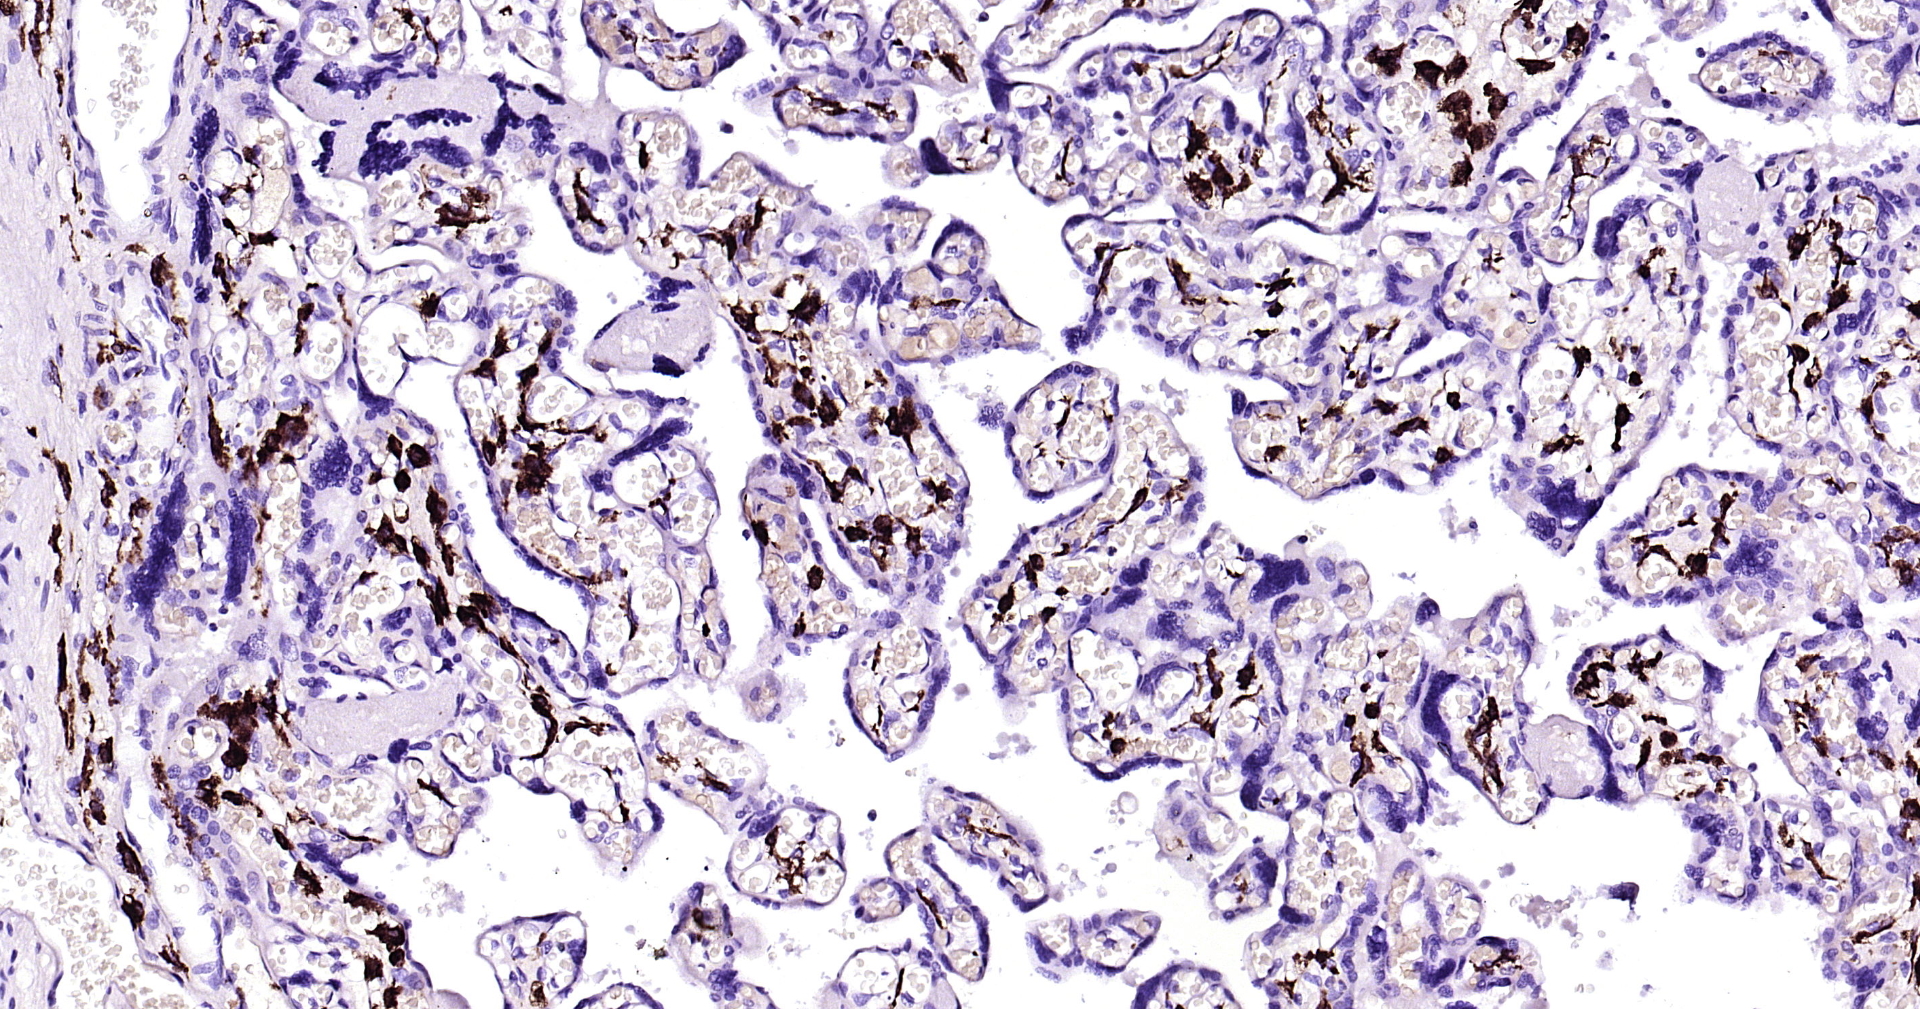

• IHC-P

• IHC

Application Dilution

IHC-P 1:200-400

IHC